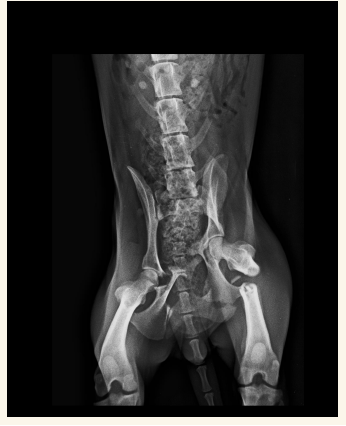

Pelvis

Fracturas y neoplasias lo mas comun. Hacer proyecciones LL, VD y Obliqua

En general se hacen proyecciones:

- Ventro-dorsal: Extender extermidades y traccionar, sin rotación axial, paralelas a la mesa, buscamos que la rotula se superponga con el surco troclear. Posicion de rana si es una fractura pelvica

- Latero-Lateral: Esponja de gomaespuma entre rodillas, estirar extermidades posteriores a caudal

Displasia de cadera:

- Más en perro que en gato

- Pasa de Laxitud articular a subluxación a EDA secundaria

- Incluir la pelvis, femur y rotulas en radiografia.

- Signos radiográficos típicos según el grado ( A---E ) Siendo A un animal sano y E una enfermedad muy avanzada